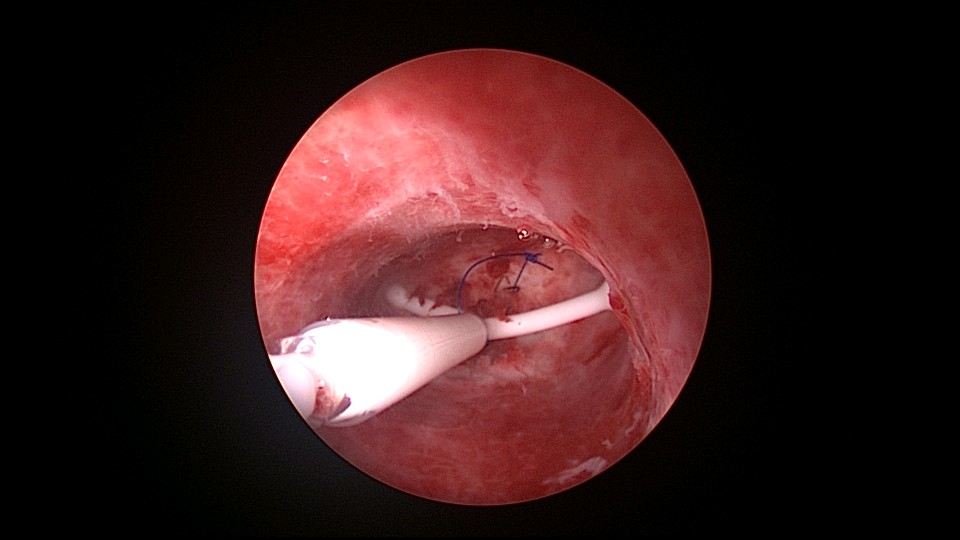

患者39岁,G6P1,顺产1次。2022年5月因输卵管间质部妊娠行宫腹腔镜手术(术前门诊医生诊断宫角妊娠),腹腔镜下行左侧输卵管间质部妊娠套扎开窗取胚术,术中见子宫腺肌症结节明显。2025年3月,严重痛经,皮下注射亮丙瑞林已3个周期,行经第6天,放置曼月乐并固定,拟行缝合固定,宫腔镜下缝合一针,牵拉确认缝合到肌层,推结时缝合处撕裂,拉出曼月乐,立即改为挂钩固定。先将不锈钢挂钩插入宫底肌层,4-0不可吸收线在曼月乐横臂中间套扎形成线圈,将曼月乐置入宫腔,异物钳夹持线圈挂到不锈钢挂钩里,原位固定曼月乐,退出宫腔镜,结束手术。2025年5月复查B超,节育环距宫底3cm,查看图片,线圈较大。节育环距宫底距离跟子宫大小、宫壁厚度、挂钩长度及线圈长度之和有关,保持这个距离不再延长即为手术成功。